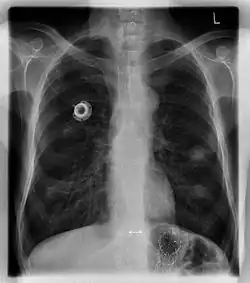

Рентгеновский снимок имплантированного порта.

Порт-система — медицинское устройство, предназначенное для введения препаратов, дренирования, забора крови и т. д. Состоит из катетера, помещенного в сосуд или полость, и соединенного с ним резервуара. Вся система располагается подкожно и обеспечивает постоянный венозный, артериальный, перитонеальный, спинальный или плевральный доступ. Для инъекций используется исключительно игла Губера с особой формой острия, которая не повреждает порт.[1]

Главными компонентами порт-системы являются: порт, состоящий из основного корпуса, силиконовой мембраны и обычно титанового резервуара, который подключается к катетеру при помощи канюли.